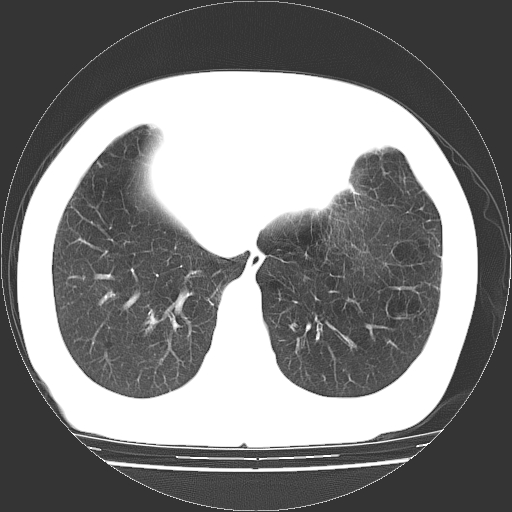

标题: CT13141:女,70岁,咳嗽、胸闷半个月。 [打印本页]

标题: CT13141:女,70岁,咳嗽、胸闷半个月。

女,70岁,咳嗽、胸闷半个月。纵隔窗未见异常,未上传。

1.小叶中心型肺气肿。

2.左肺下舌段感染性病变。

肺大疱的壁甚薄,由肺泡的扁平上皮细胞组成,也可能仅为纤维性膜。可与多种肺气肿并存,常见于间隔旁侧或细叶旁肺气肿,可伴有碳末沉着,如煤矿工人尘肺,或不伴有碳末沉着,如瘢痕组织肺气肿。根据病理形态将肺大疱分为三种类型。

ⅰ型:狭颈肺大疱。突出于肺表面,并有一狭带与肺相连。因为支气管瘢痕组织形成的活瓣性阻塞,肺大疱体积增大系由于肺泡侧支通气和气体滞留。ⅰ型肺大疱壁薄,常由胸膜和结缔组织形成,多发生于中叶或舌叶,也常见于肺上叶,可能由于该部位胸腔负压大,常规胸片即可发现肺大疱的存在。

ⅱ型:宽基底部表浅肺大疱。位于肺表层,在脏层胸膜与气肿性肺组织之间。肺大疱腔内可见结缔组织间隔,但它不构成肺大疱的壁,可见于肺的任何部位。

ⅲ型:宽基底部深位肺大疱。结构与ⅱ型相似,但部位较深,周围均为气肿性肺组织,肺大疱可伸展至肺门,可见于任何肺叶。

当肺大疱体积增大时,周围肺组织受压迫并引起肺脏移位。受压肺组织在x线胸片上,表现为肺大疱周围密度增高阴影。以上三型均见于慢性支气管炎。小叶中心型肺气肿不并发肺大疱。下叶肺大疱常见于有并发症的煤矿工人尘肺和融合性矽肺。